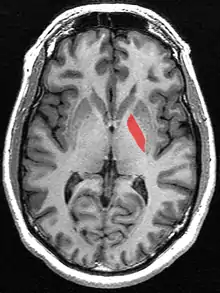

Горизонтально орієнтоване МРТ-зображення, що показує бліду кулю.

Бліда куля